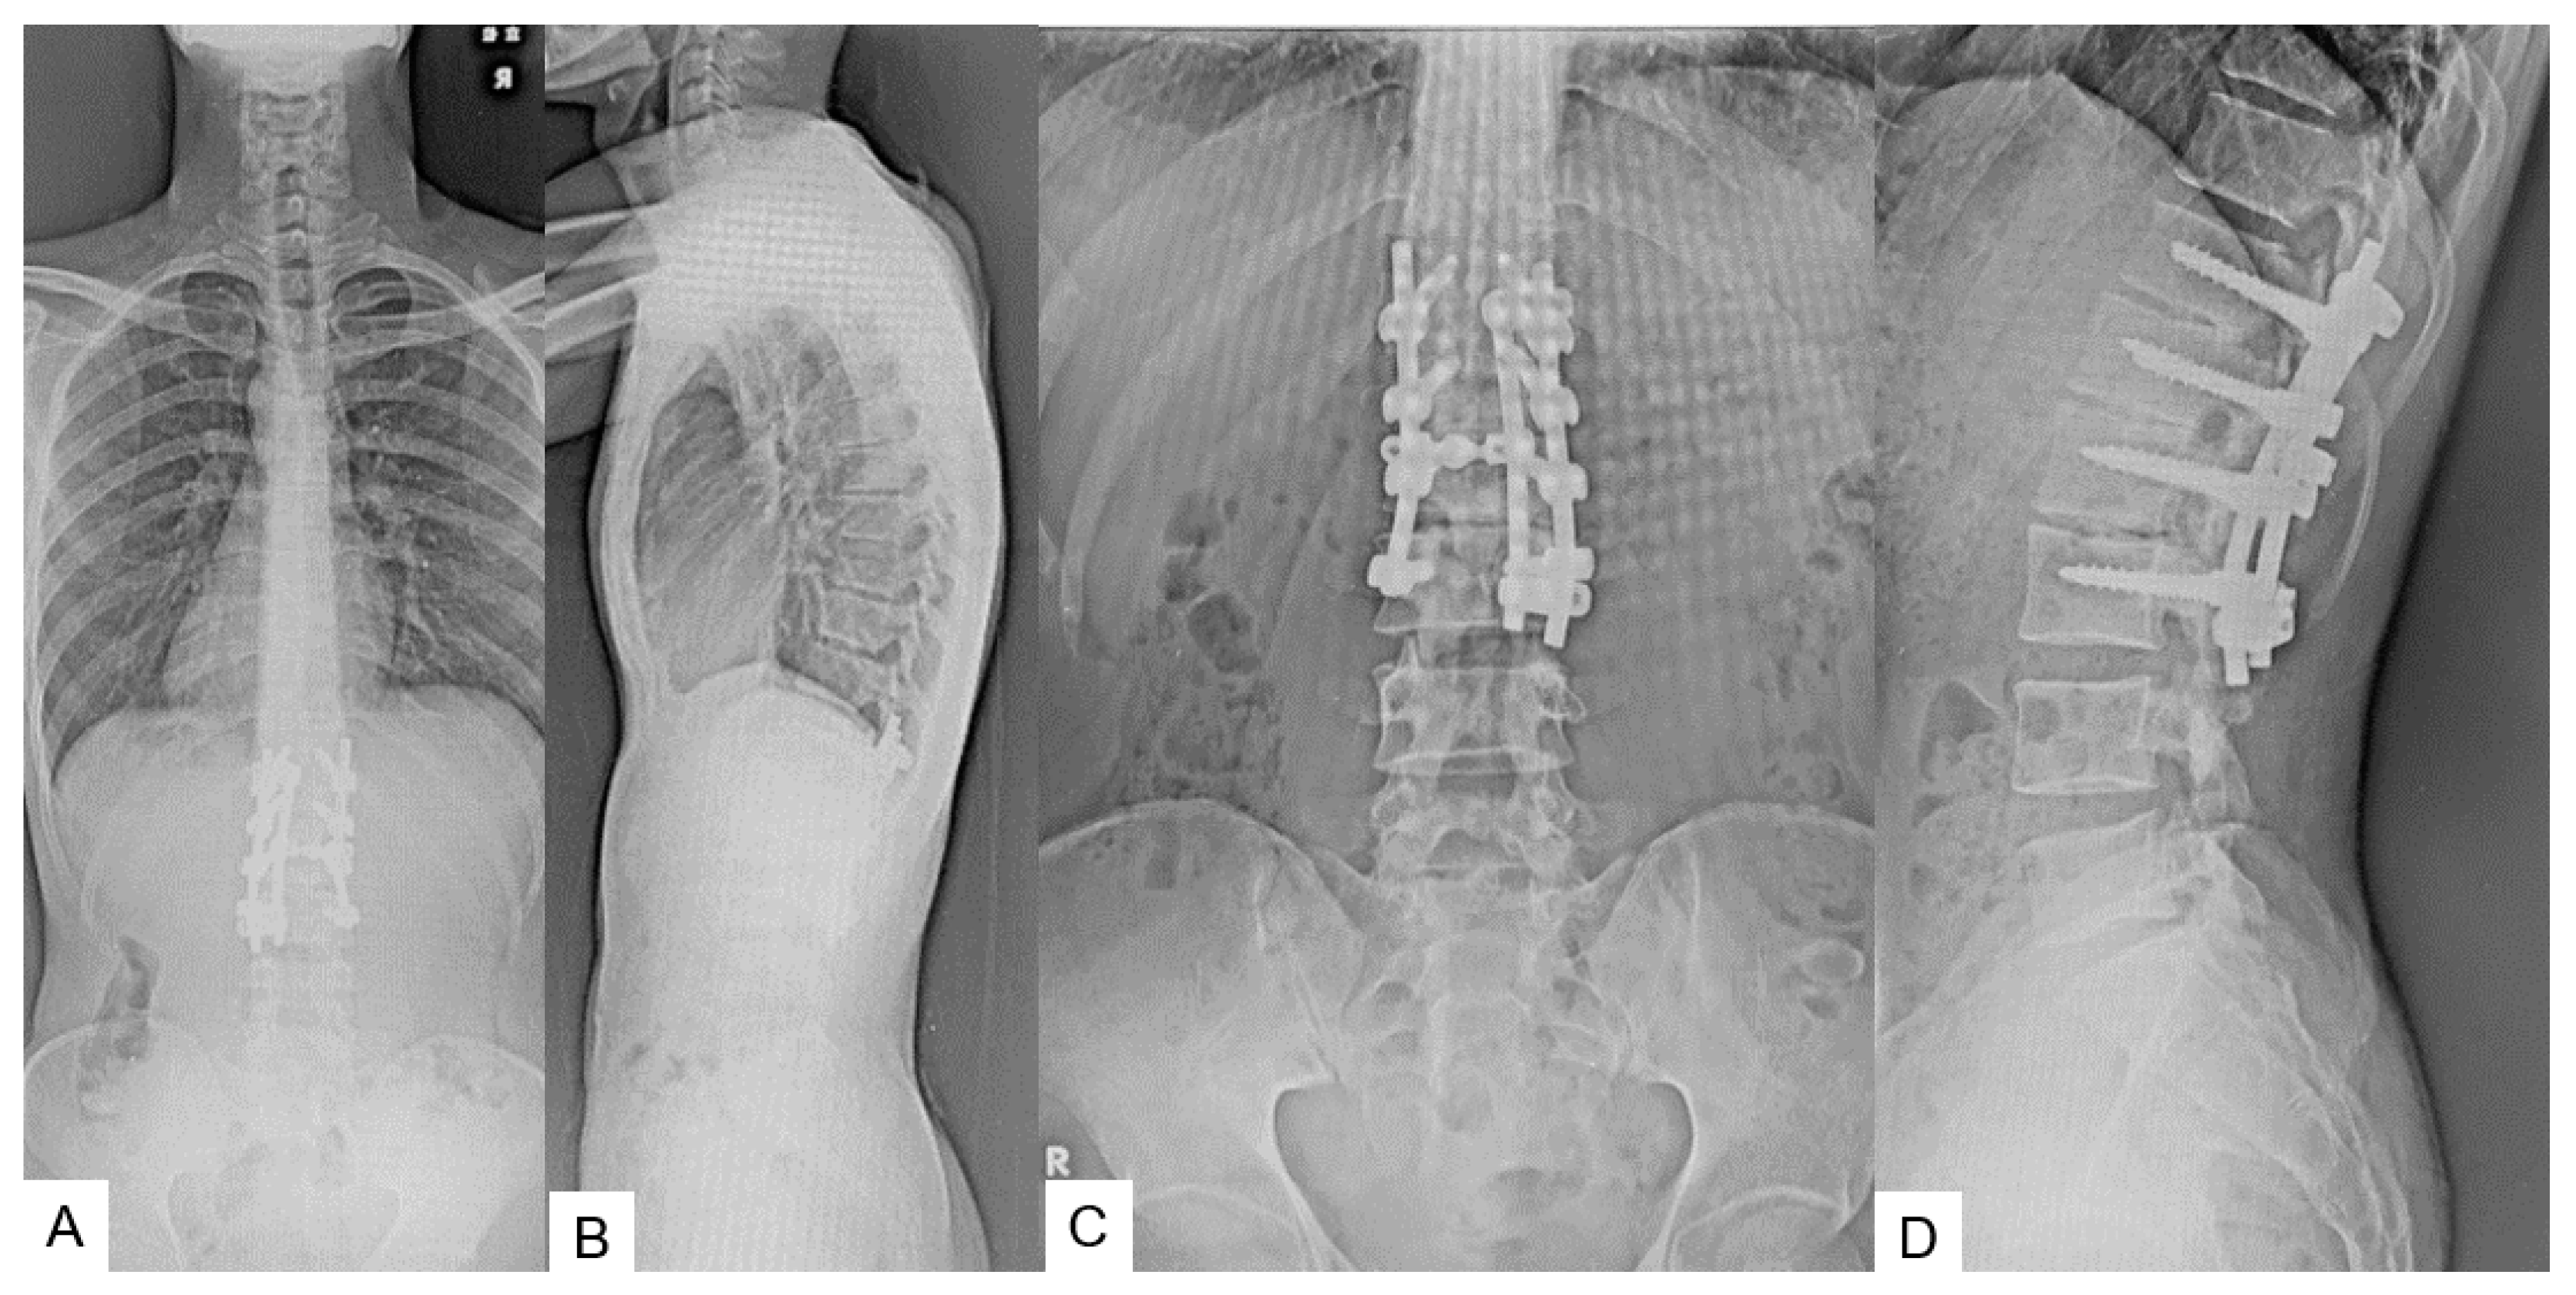

2.5. Postoperative Images

2.6. One Year Follow-Up